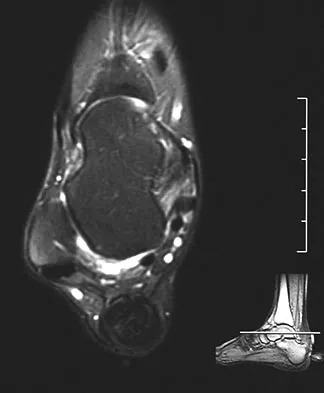

A 40-year-old woman has a symptomatic mass on the anterior aspect of the ankle. She reports no constitutional symptoms. An MRI scan is shown in Figure 12. What is the most likely diagnosis?

Explanation